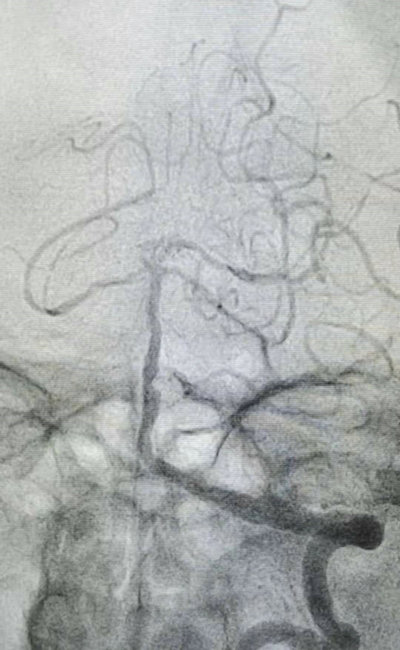

1月7日下午,介入科马晓欧主任和杜友利医生,首先为董先生实施了基底动脉狭窄球囊扩张支架植入术,狭窄部位扩张满意后植入支架。术后患者神志清楚,言语流利,四肢活动自如,恢复良好。(供稿:介入科 杜友利 编辑:宣传科 张宁 )

介入科主任马晓欧(右)、主治医师杜友利为患者行基底动脉狭窄球囊扩张支架植入术

支架植入术后